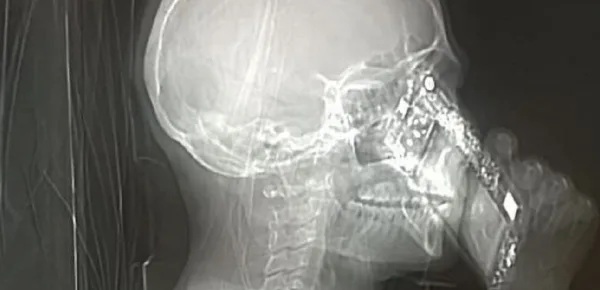

Nonostante l'interruzione dall'esame tomografico, l'apparecchio ha comunque registrato l'immagine che mostra la donna intenta a rispondere al suo cellulare.

I medici della struttura ospedaliera di Napoli hanno, cosi, ben pensato di mettere sul web la fotografia non solo per divertire gli utenti, ma anche per avvisare tutta la popolazione di quanto il telefono possa essere pericoloso, soprattutto in momenti delicati come quello di una Tac. Nonostante la donna non abbia rispettato le regole dell'esame i medici hanno comunque deciso di farle ripetere la tomografia, scoprendo, per fortuna, che la signora non soffriva di nessuna problematica particolare, sarà proprio lo smisurato uso del telefono cellulare a provocarle i frequenti mal di testa?